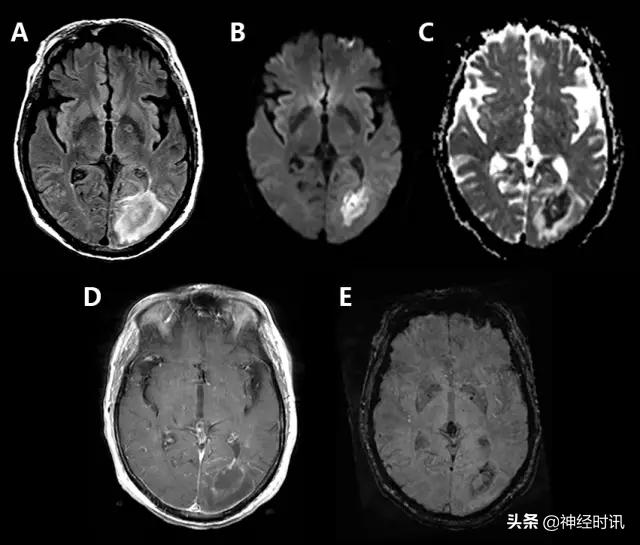

图2 一例66岁男性,癫痫发作伴意识状态改变、急性失语和右侧凝视,拟诊脑卒中并给予IV-tPA治疗。左侧病灶情况下的右侧凝视可提示癫痫发作。他的入院MRI显示左侧额顶叶皮层和皮层下白质弥散受限(A和B)和水肿(C)。他的症状和影像学(图像未提供)显示在出院前完全缓解。

图3 一例49岁女性,突然醒来出现言语不清。最初CT报告左侧MCA区域脑梗死伴左侧MCA高密度(A),MRI显示非强化(B)、T2-FLAIR高信号(C)的膨胀性病灶伴弥散增加(D-DWI,E-ADC)。活检显示为间变性少突胶质细胞瘤。